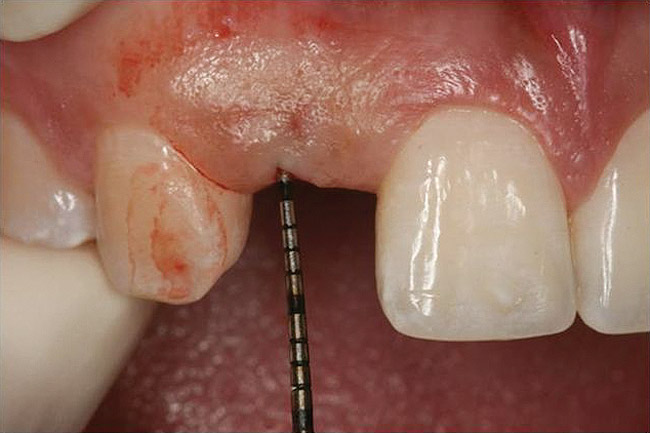

Figure 10  Clinical examination of the bound edentulous space: Measurement of the distal (Fig 10) and mesial (Fig 11) interproximal tissue height using a periodontal probe supplements data obtained from the periapical radiograph. Estimation of the buccal tissue thickness (bone sounding) is performed at the determined location of the gingival zenith using a guide developed from the diagnostic waxing (Fig 12).

Figure 11   Clinical examination of the bound edentulous space: Measurement of the distal (Fig 10) and mesial (Fig 11) interproximal tissue height using a periodontal probe supplements data obtained from the periapical radiograph. Estimation of the buccal tissue thickness (bone sounding) is performed at the determined location of the gingival zenith using a guide developed from the diagnostic waxing (Fig 12).

Figure 12   Clinical examination of the bound edentulous space: Measurement of the distal (Fig 10) and mesial (Fig 11) interproximal tissue height using a periodontal probe supplements data obtained from the periapical radiograph. Estimation of the buccal tissue thickness (bone sounding) is performed at the determined location of the gingival zenith using a guide developed from the diagnostic waxing (Fig 12).